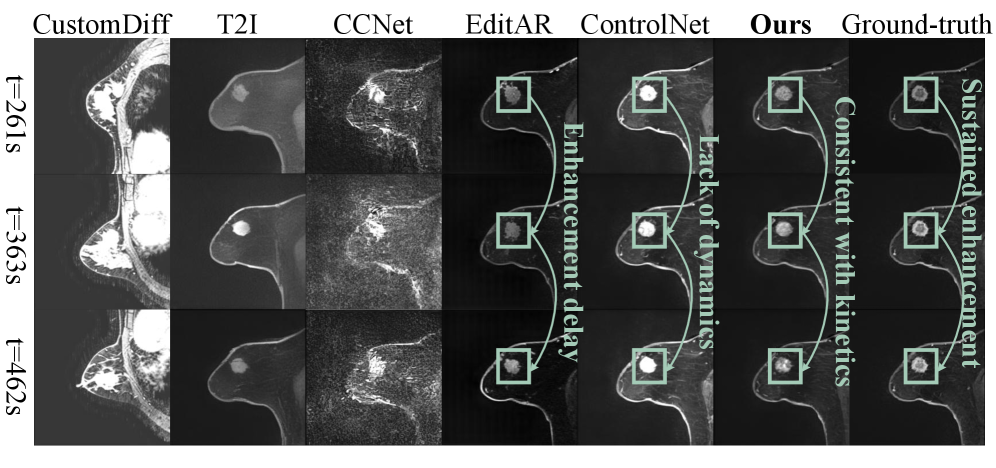

Visualization Results Analysis As shown in Fig.4 and Fig.5, the visualization sequences of both datasets demonstrate that our method achieves high spatial reality and natural kinetics, both closely matching the ground-truth. CustomDiff and T2I generated images with severe deviations from the ground-truth, suffering from blurred organ contours and distorted dynamic enhancement gradients of contrast agents. CCNet failed to converge, leading to excessively smooth images, severe spatial structural distortion, and the appearance of color blocks, which is consistent with the previously analyzed characteristic of high PSNR. EditAR and ControlNet have normal spatial structures, but their kinetics both deviate from the normal pattern. More visualization results are in Supplementary.

Figure 5: Visualization results in Breast DCE-MRI: The visualization results achieves temporal consistent (connected green boxes) with contrast agent kinetics, demonstrating superior fidelity in breast DCE-MRI sequence generation.

7.2.3 Visualization Results for Different Enhancement Patterns in Breast DCE-MRI

The two breast DCE-MRI visualization cases shown in Fig.13 and Fig.14 demonstrate that our CEKWorld simulates clinically meaningful kinetic patterns, showing strong potential for downstream risk-stratification tasks since lesion malignancy is closely associated with characteristic enhancement patterns [36, 44]. In both figures, our model accurately reproduces the temporal trajectories observed in ground-truth DCE-MRI sequences, whereas competing methods exhibit severe issues such as incorrect enhancement magnitude, temporal shifts, or lack of temporal evolution. In Fig.13, the ground-truth exhibits a gradually rising and persistently elevated curve, typical of a persistent enhancement pattern, often associated with benign or low-risk lesions. Our method produces consistent, sustained enhancement across all time points, faithfully matching the true kinetics. In contrast, EditAR shows enhancement delay, and ControlNet lacks any meaningful temporal progression, failing to reproduce the low-risk kinetic profile. This demonstrates our model’s ability to reconstruct benign-like temporal behavior. In Fig.14, the lesion shows rapid initial enhancement followed by clear washout, a hallmark of malignant or high-risk lesions. Our method correctly captures this dynamic pattern: a sharp early rise followed by a decline consistent with the ground truth. EditAR suffers from excessive enhancement and fails to show the washout phase, while ControlNet exhibits collapsed or weakened dynamics, failing to reproduce the malignant-typical kinetic transition. Together, these two visualization examples show that our method not only preserves spatial fidelity but also faithfully models critical DCE-MRI temporal dynamics. Because low- and high-risk lesions exhibit fundamentally different enhancement trajectories, the ability of our model to reconstruct these dynamics suggests strong potential for downstream tasks such as risk stratification, benign-vs-malignant discrimination, and clinical subtype prediction.